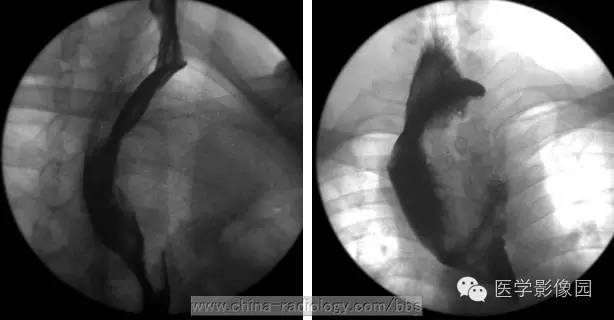

X线食管钡餐检查是本病的主要诊断方法,结合临床表现,往往可以一次造影确诊。

钡餐造曩所见取决于肿瘤的大小形态和生长方式。腔内充盈缺损是主要表现,缺损呈圆形或椭圆形,边缘光滑锐利,与正常食管分界清楚。充盈缺损上下端与正常食管交界角随肿瘤突入管腔多少而呈锐角或轻度钝角。正位时与食管长轴垂直的肿瘤轮廓由于钡餐的对比显示为半圆形阴影,出现“环形征”。肿瘤处粘膜被顶出,皱襞消失,该处钡剂较周围少,成一薄层,形成“瀑布征”或“涂抹征”。肿瘤大的在充盈缺损所在部位可见软组织阴影,透视下观察钡剂通过情况,在肿物上方稍停一下,然后在肿瘤与对侧食管壁间呈带状通过,状如小沟。肿瘤附近的食管壁柔软,收缩良好,近端食管不扩张。

多发性平滑肌瘤或马蹄形肿物环抱食管,使管腔凹凸不平,粘膜显示不清,要注意与食管癌的鉴别。后者管壁僵硬,充盈缺损不规则,有粘膜破坏及龛影等。

食管平滑肌瘤与纵隔肿瘤处压改变的不同在于:后者管壁处充盈缺损较浅,切线位肿物与管壁间的钡影成钝角,食管双侧壁同时向一侧偏移。